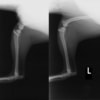

■ 症例20 ポメラニアン 8ヶ月 1.8kg

左右膝蓋骨脱臼 グレードⅢ

2ヶ月前から間欠的跛行が認められ、両膝の膝蓋骨脱臼整復術を行った。

手技は縫工筋及び内側広筋の解放、脛骨粗面の外側転位、滑車ブロック形造溝術、内外側関節包の縫縮を選択し実施した。

右側の膝蓋骨脱臼は上記手技で整復されたものの、左側はそれのみでは膝蓋骨が浮く様子が認められた。その為、PDS縫合糸にて膝蓋靱帯を1糸のみ縫合し、靱帯の縫縮を行った。